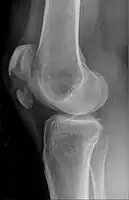

Patella fracture

| A fracture of the patella seen on a lateral view | |

Diagnosis is based on symptoms and examination, which typically reveals a swollen knee with reduced movement and a tender kneecap.[5] A fracture is subsequently confirmed with X-rays usually taken from different angles.[3] In children an MRI may be required.[3]